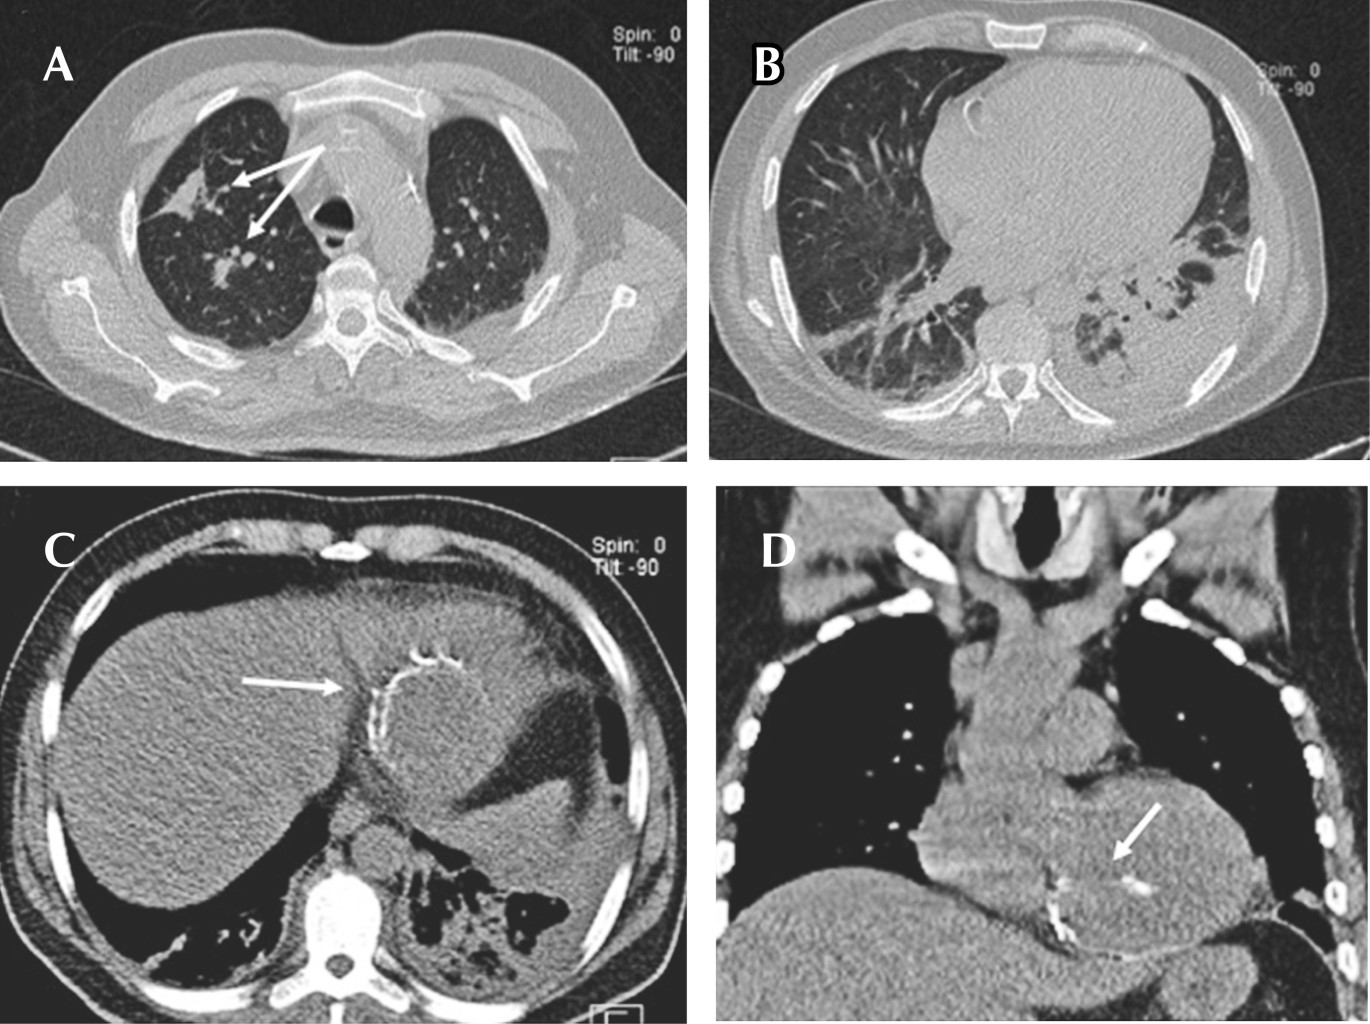

Endocarditis y espondilodiscitis como complicación de ruptura de aneurisma ventricular postinfarto

Aneurisma ventricular, infarto, endocarditis, espondilodiscitis.

El aneurisma ventricular postinfarto se define como una dilatación del ventrículo izquierdo o derecho en forma sacular que puede provocar su ruptura a nivel de la pared o septum ventricular y puede predisponer a endocarditis debido a la producción de turbulencias ocasionadas por cortocircuitos que ocasionan daño del tejido endocárdico con la consecuente colonización bacteriana y embolismos sistémicos. Una vez confirmado el diagnóstico, debe otorgarse tratamiento antibiótico y, en caso de complicaciones, valorarse el tratamiento quirúrgico. Se reporta el caso de un paciente masculino con antecedente previo de infarto agudo de miocardio, el cual acudió a urgencias por presentar datos de respuesta inflamatoria sistémica, evidenciándose endocarditis en válvula tricúspide y un aneurisma ventricular roto, condicionando fenómenos embólicos a columna dorsal, por lo que requirió tratamiento quirúrgico.

Figura 1